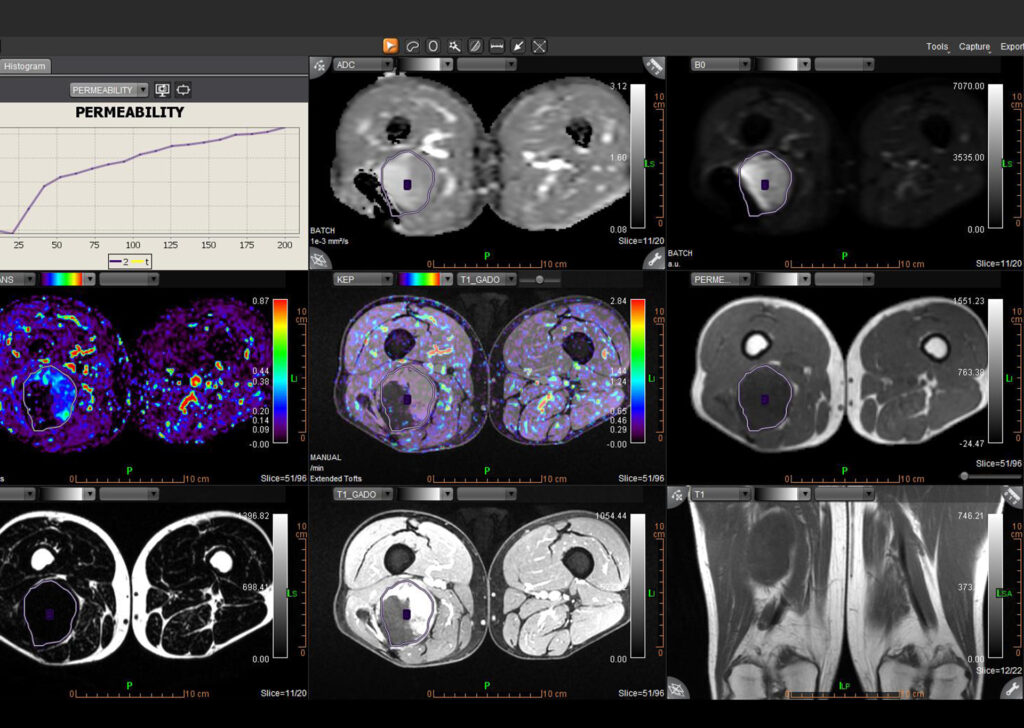

MR Body Full

MR Head and Neck, MR Breast, MR Prostate, MR Rectum, MR MSK, MR Female Pelvis, Advanced Multiparametric Analysis, Dynamic Contrast Enhanced Permeability, Diffusion Weighted Imaging, Kinetics, Longitudinal Analysis, Intravoxel Incoherent Motion, Metabolic, and Onco-Inflammatory.

MR Prostate

Olea MR Prostate application exceeds specialists’ expectations for lesion detection, characterization and staging.